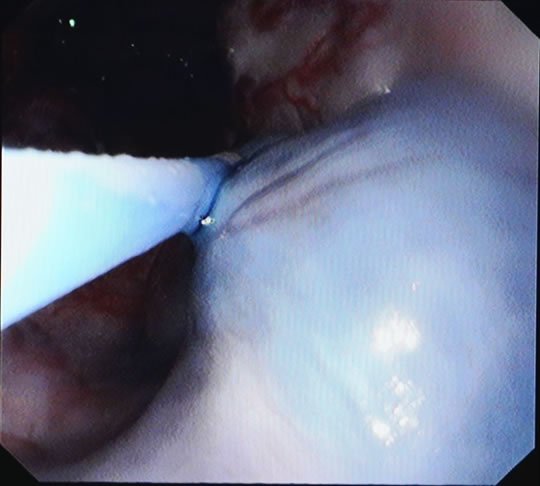

郎溪县人民医院成功开展了胃镜下食管静脉曲张硬化术

郎溪县人民医院消化内科与南京中大医院协作,成功开展了胃镜下食管静脉曲张硬化术。该技术适用于肝硬化合并食管静脉曲张破裂出血及预防再出血患者,减少患者反复出血带来的痛苦,提高生存质量。